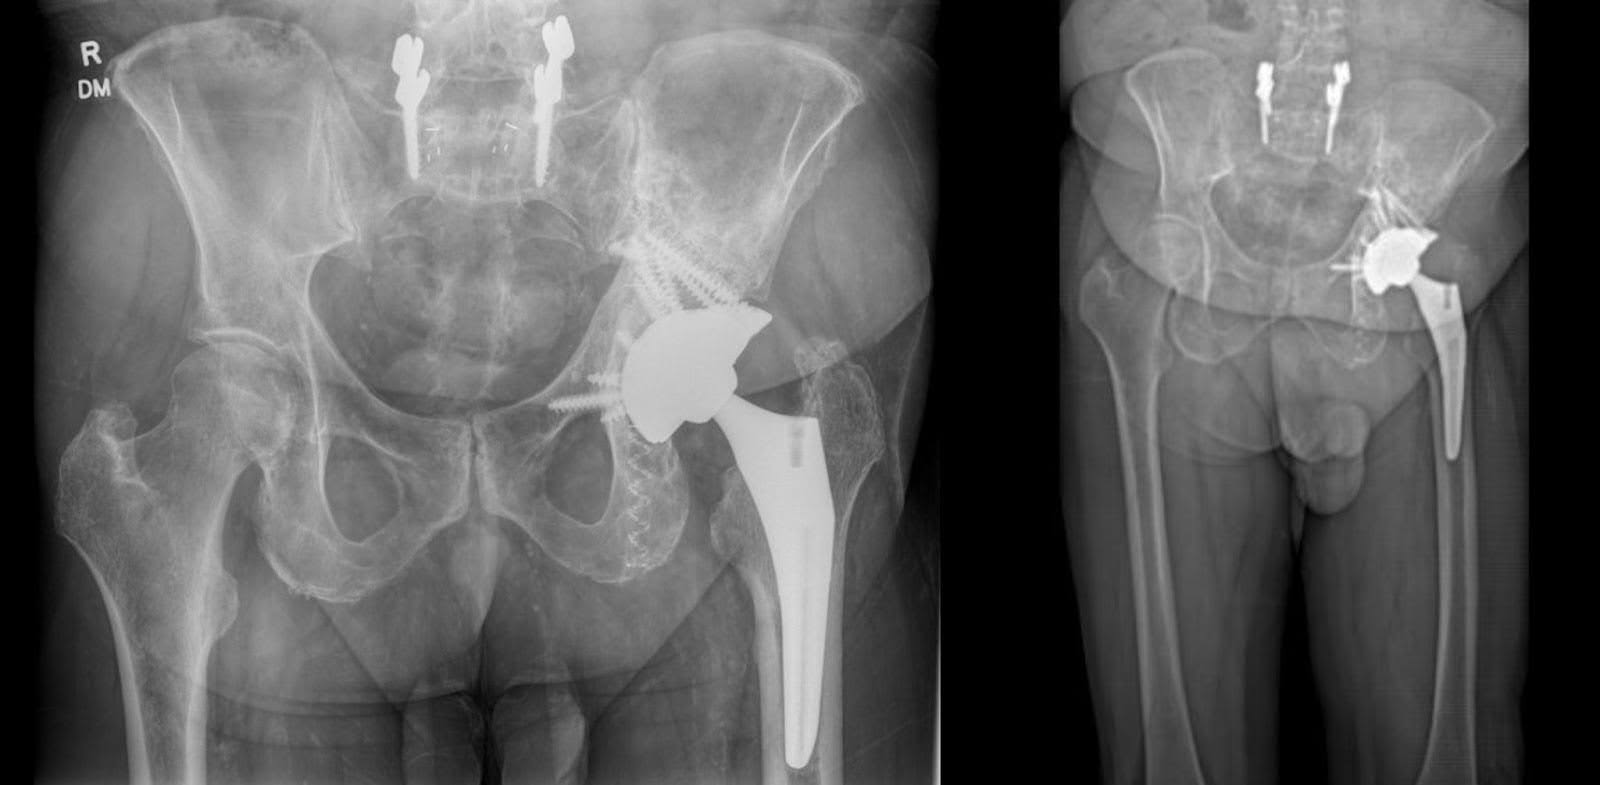

Seis meses após a cirurgia, o paciente demonstrou amplitude de movimento completa no quadril esquerdo, porém relatando dor localizada durante a rotação interna. A flexão e extensão do quadril estavam dentro dos limites da normalidade. Clinicamente, o paciente exibiu comprimento de perna quase adequado, mas exibiu uma marcha antálgica com comprimento de passada esquerdo reduzido em comparação com o direito. Apesar de participar de mais de 30 sessões de fisioterapia, o paciente experimentou fadiga e dor moderadas durante a deambulação, necessitando de pausas frequentes após caminhar distâncias moderadas. A dor na virilha esquerda e na lateral do quadril ainda aumenta durante os períodos translacionais e prolongados de atividade. As radiografias da articulação do quadril e da pelve revelaram ATQ esquerda bem alinhada com aumentos de tântalo em posições ideais, sem sinais de soltura (Figura 5).

Figura 5. Radiografia AP da pelve seis meses após a cirurgia. Alinhamento estável após artroplastia total do quadril esquerdo com aumento acetabular, juntamente com fixação do osso isquiático e ilíaco esquerdo com hastes fotodinâmicas. Nenhuma evidência de fratura periprotética.